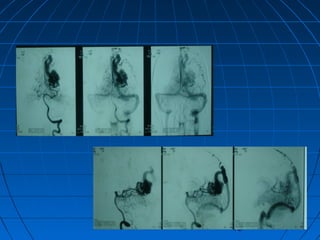

 ST: 43 yaşında kadın hastaST: 43 yaşında kadın hasta

 BaşağrısıBaşağrısı (akut şiddetli, birkaç saat(akut şiddetli, birkaç saat

içinde)içinde)

 GKS 13 (WFNS grade 2)GKS 13 (WFNS grade 2)

 Fisher grade IIIFisher grade III

CERRAHİCERRAHİ

 Sağ pterional trans-sylvian yaklaşımSağ pterional trans-sylvian yaklaşım

 Proksimal ICA Anevrizması kliplendiProksimal ICA Anevrizması kliplendi